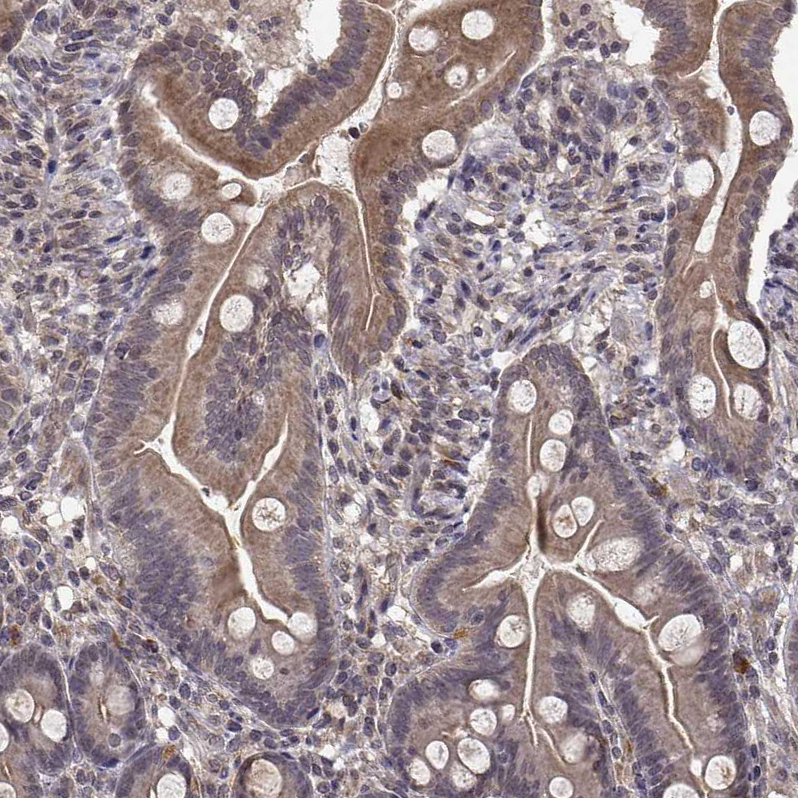

Immunohistochemical staining of human gallbladder shows moderate cytoplasmic positivity in glandular cells.